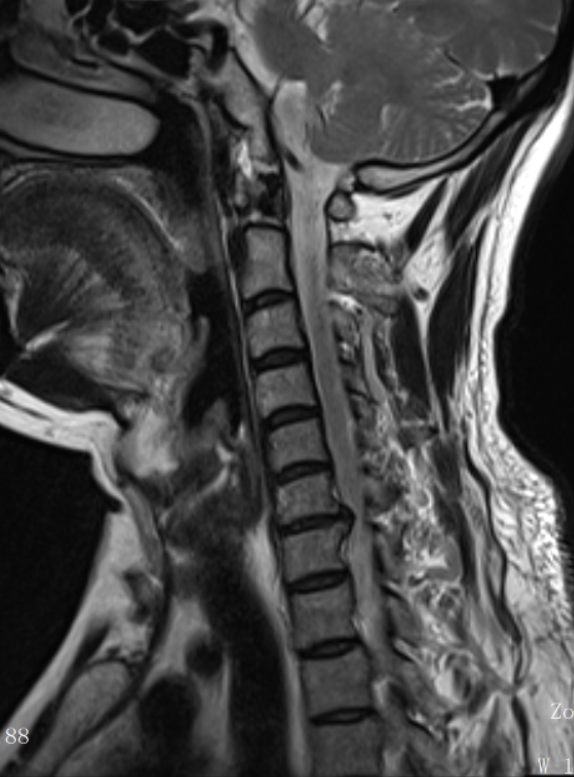

马先生随即到中山市第六人民医院就诊,脊柱外科漆海如主任医师经过详细的体格检查和颈椎核磁共振(MRI)检查后,诊断为“颈椎间盘突出症”,突出的椎间盘严重压迫了神经根,这正是导致患者剧痛的元凶。

▲术前颈椎MR示颈6/7椎间盘突出